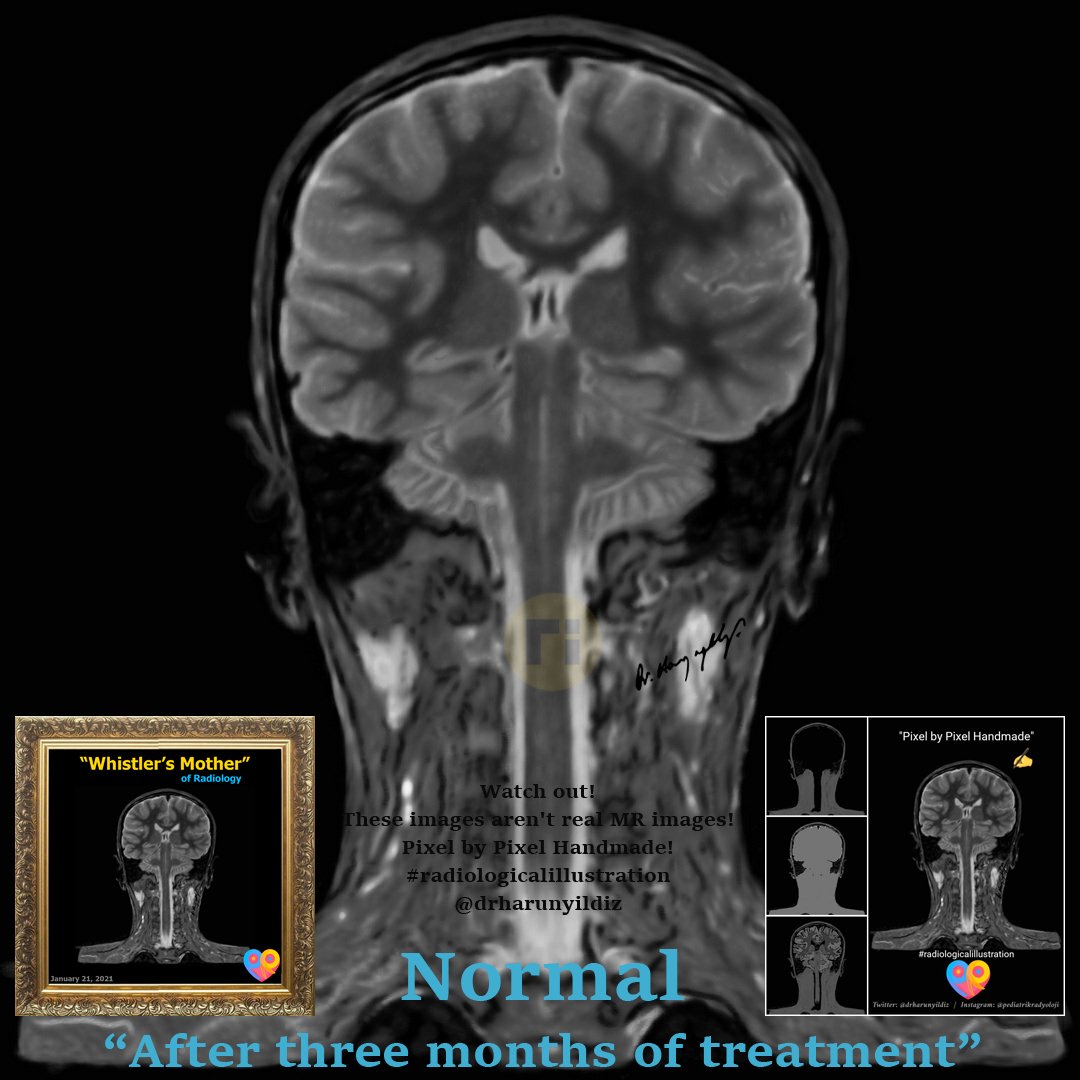

“Waterfall Sign" / Neuro-Behçet doi.org/10.1016/j.radc… ajnr.org/content/quiz/1… #radiologicalillustration ✍️ Pixel by Pixel Handmade!

drharunyildiz's tweet image. “Waterfall Sign" / Neuro-Behçet